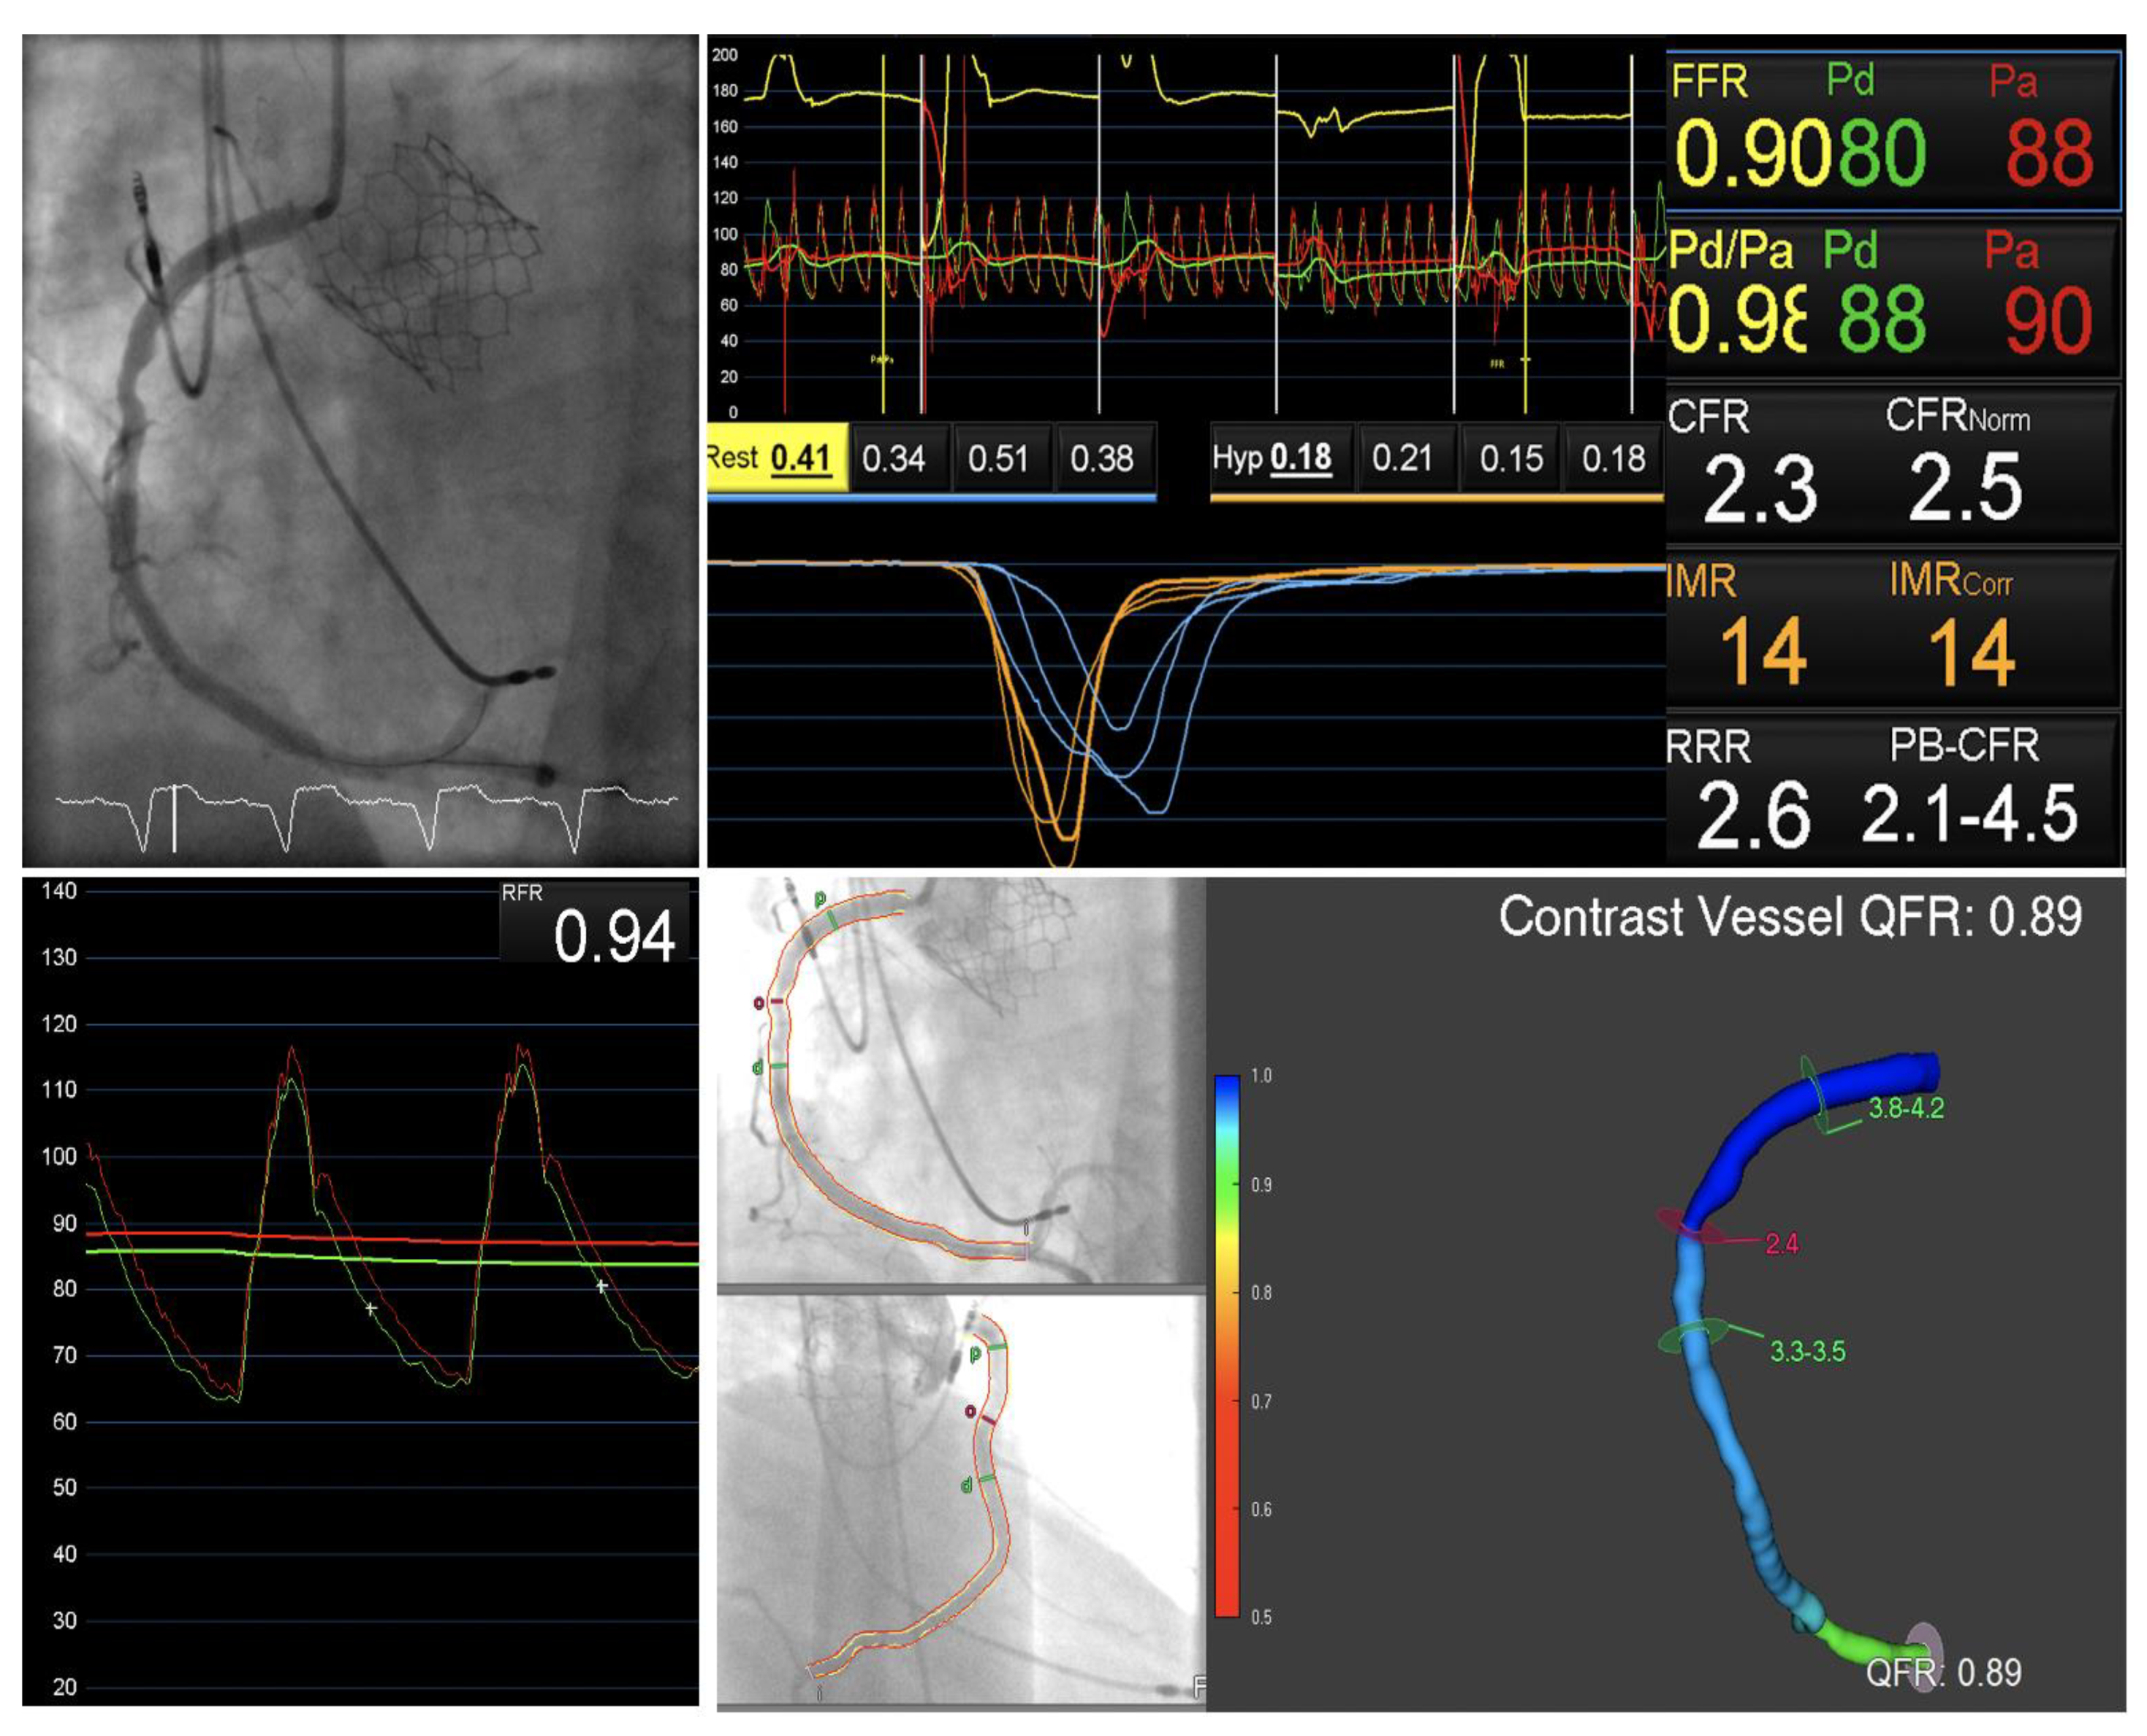

3.1. Invasive Physiological Assessment

3.3. Quantitative Flow Ratio in Presence of Aortic Stenosis

3.4. FFRCT in Presence of Aortic Stenosis